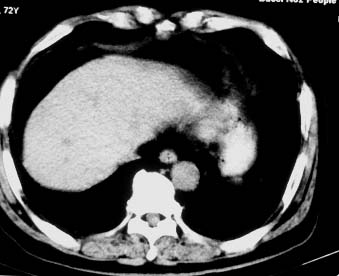

男 56 腹部不舒

典型肝硬化:1、肝各叶大小的比例失常;2、肝表面明显凹凸不整,边缘变钝;3、肝实质密度一般与正常肝无明显改变;4、肝裂增宽;5、门静脉增宽,脾静脉扩张扭曲;6、脾脏虽然不大,但不是所以肝硬化的脾脏都增大。

典型肝硬化:1、肝各叶大小的比例失常;2、肝表面明显凹凸不整,边缘变钝;3、肝实质密度一般与正常肝无明显改变,但肝右叶似可见再生结节影;4、肝裂增宽;5、门静脉增宽,脾静脉扩张扭曲;6、脾脏增大. 脾脏大小的标准有:1脾脏的左右径(大于5个肋单元) 2脾脏的宽度 3脾脏的上下径(超过肝下缘) 请参考.

典型肝硬化:1、肝各叶大小的比例失常;2、肝表面明显凹凸不整,边缘变钝;3、肝实质密度一般与正常肝无明显改变,但肝右叶似可见再生结节影;4、肝裂增宽;5、门静脉增宽,脾静脉扩张扭曲;6、脾脏增大.

典型肝硬化:1、肝各叶大小的比例失常;2、肝表面明显凹凸不整,边缘变钝;3、肝实质密度一般与正常肝无明显改变,但肉眼观察与脾胀密度低或等密度;4、肝裂增宽;5、门静脉增宽,脾静脉扩张扭曲;6、脾脏增大.

肝硬化表现符合,肝脾ct值有倒置,考虑局灶性肝脂肪浸润